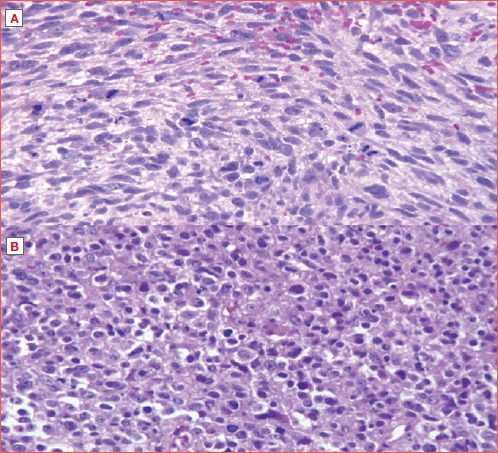

Generally, LCS are slow-growing tumours with relatively low malignant potential. However, high-grade (G3), dedifferentiated (DD), and myxoid (MY) LCS are considered more aggressive subtypes due to their higher rates of local recurrence, distant metastases (DM), and relatively poor prognosis 8 (Cover figure). Metastases from LCS have been described in the literature in up to 10% of cases, although some studies reported a lower incidence of 1.9% 1. Metastatic patterns of LCS are typically haematogenous with lung and bone being the most prevalent metastatic sites. Considering the cervical lymph nodes, regional metastases are rare, and neck dissection must be reserved for cases in which diagnostic imaging suggests clinical lymph node(s) involvement 11.